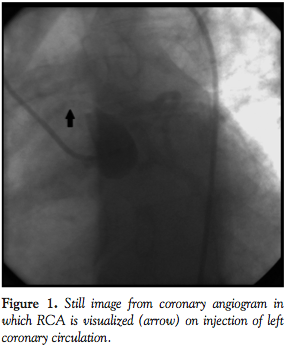

injection of the left coronary circulation (Figure 1; Video 1, available at www.invasivecardiology.com). A coronary CT angiogram (CCTA) showed an ectopic RCA originating from the left coronary sinus traversing between the pulmonary artery and aorta (Figures 2 and 3).